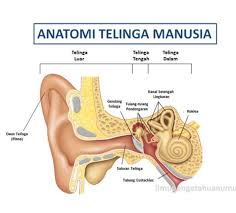

Otomikosis adalah infeksi telinga yang disebabkan oleh jamur. Dikenal juga sebagai otitis eksternal fungal. Otomikosis umumnya mengenai liang telinga luar yang merupakan lingkungan ideal untuk pertumbuhan jamur. Otomikosis biasanya hanya menyerang salah satu telinga. Namun, pada beberapa kasus, kondisi ini juga dapat terjadi di kedua telinga. Otomikosis juga dapat mengenai telinga tengah. Otomikosis dapat dijumpai di berbagai wilayah demografi dengan kelembaban tinggi di daerah tropis dan subtropik.

Otomikosis ditandai dengan keluhan nyeri (otalgia), keluar cairan (otorrhea), gangguan pendengaran hingga hilang pendengaran, telinga rasa penuh, gatal dan mendengung (tinitus). Tetapi otomikosis dapat pula tanpa keluhan. Otomikosis yang tidak bergejala dan tidak ditangani berpotensi menyebabkan hilangnya pendengara. Pada pemeriksaan menggunakan otoskop dapat ditemukan pembengkakan (edema), kemerahan (hiperemis) kulit liang telinga luar, pengelupasan epitel superfisial, penumpukan debris yang berbentuk hifa, serta supurasi